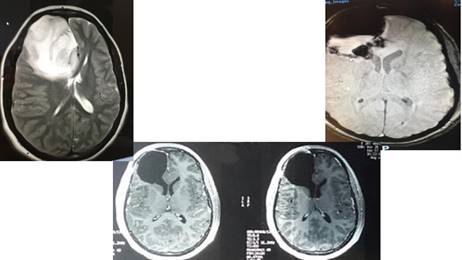

Figura 7: Resonancia Magnética corte sagital. Arriba a la izquierda puede verse la voluminosa masa tumoral. Arriba a la derecha, la primer resección amplia, pero incompleta. Abajo, la ampliación de la resección llegando hasta el ventrículo con conservación funcional completa.